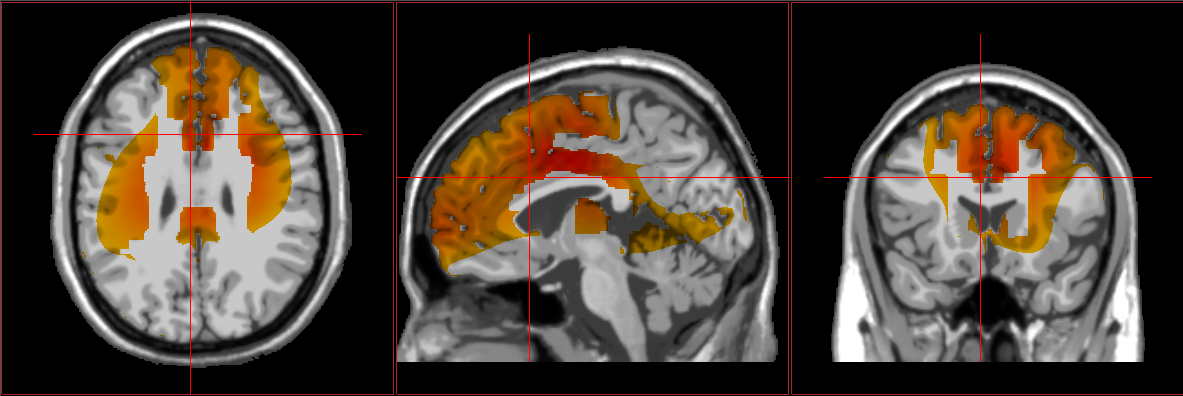

EEG brain scans showing typical results from autism loreta neurofeedback showing signs of autism Autism / spectrum results from loreta neurofeedback

Atypical connectivity patterns within the brain seem to explain some of the challenges experienced by those with ASD. EEG and fMRI imaging demonstrate a surplus of synapses and connections between certain regions, which can make it difficult for a person to switch between tasks and ideas. This might underlie the repetitive and restrictive behaviors often exhibited by those with ASD. Hyperconnectivity and inefficient communication between neurons can also affect other important processes such as motor control, interpretation of social cues, and language production/analysis.

Areas of the brain associated with sensory integration and processing also tend to show more “randomized” activity in the EEGs of those with ASD. Such activity can make it more difficult for individuals to process and tolerate sensory information. Additionally, some ASD individuals show an excess of slow brainwave frequencies (e.g., delta/theta) throughout the brain, leading to significant impairments in learning and cognitive processing. They may also show an excess of faster frequencies in regions related to stress and anxiety, leading to heightened emotional reactivity.

Furthermore, the brains of those diagnosed with ASD often show reduced activation levels within imitation-related brain areas when compared to individuals without ASD. Limited functioning of these areas is thought to contribute to a variety of ASD symptoms, especially those related to social interactions.